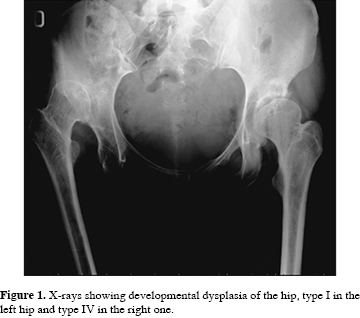

In October 2004, a 41-year-old female with severe hip pain affected by bilateral DDH type I in the left hip and type IV in the right hip according to the Crowe classification came to our institute for clinical examination.

The patient had a positive bilateral Trendelemburg sign and her hips were highly limited in their range of motion. Particularly, the right hip was limited to 60o in flexion and to 5o in internal and external rotations. Preoperative Harris Hip Score (HHS) was 53 for the right and 62 for the left hip, respectively.

A 52-mm limb-length discrepancy was measured on anteroposterior preoperative radiographs (Figura 1).